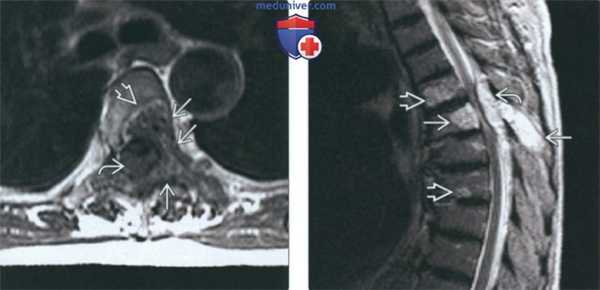

(Слева) На аксиальной МРТ (Т1 ВИ) определяются признаки агрессивной гемангиомы грудного позвонка с распространением в задние отделы и эпидуральное пространство. Жир визуализируется лишь в одной области. Точечный рисунок обусловлен трабекулами в гемангиоме.

(Справа) На сагиттальной МРТ (Т2 ВИ) визуализируется агрессивная гемангиома с гиперинтенсивным сигналом и легко различимым крупным эпидуральным компонентом. Видны также другие гемангиомы.